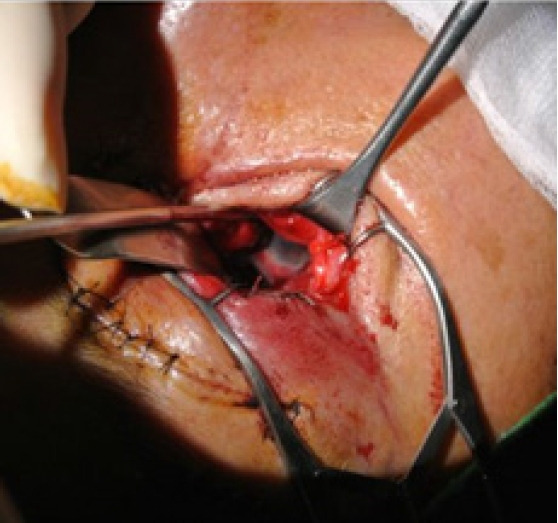

Orbital floor fractures are commonly encountered, but the dislocation of the eyeball into the maxillary sinus is relatively rare. When it does occur, globe dislocation can have serious consequences, including vision loss, enucleation, and orbito-ocular deformity. Immediate surgical intervention is typically attempted when possible. However, severe comorbidities and poor general health can delay necessary surgery. In this report, we present the surgical outcomes of a 70-year-old woman who received delayed treatment for traumatic eyeball dislocation into the maxillary sinus due to a subarachnoid hemorrhage and hemopneumothorax. Additionally, we propose a treatment algorithm based on our clinical experience and a review of the literature.